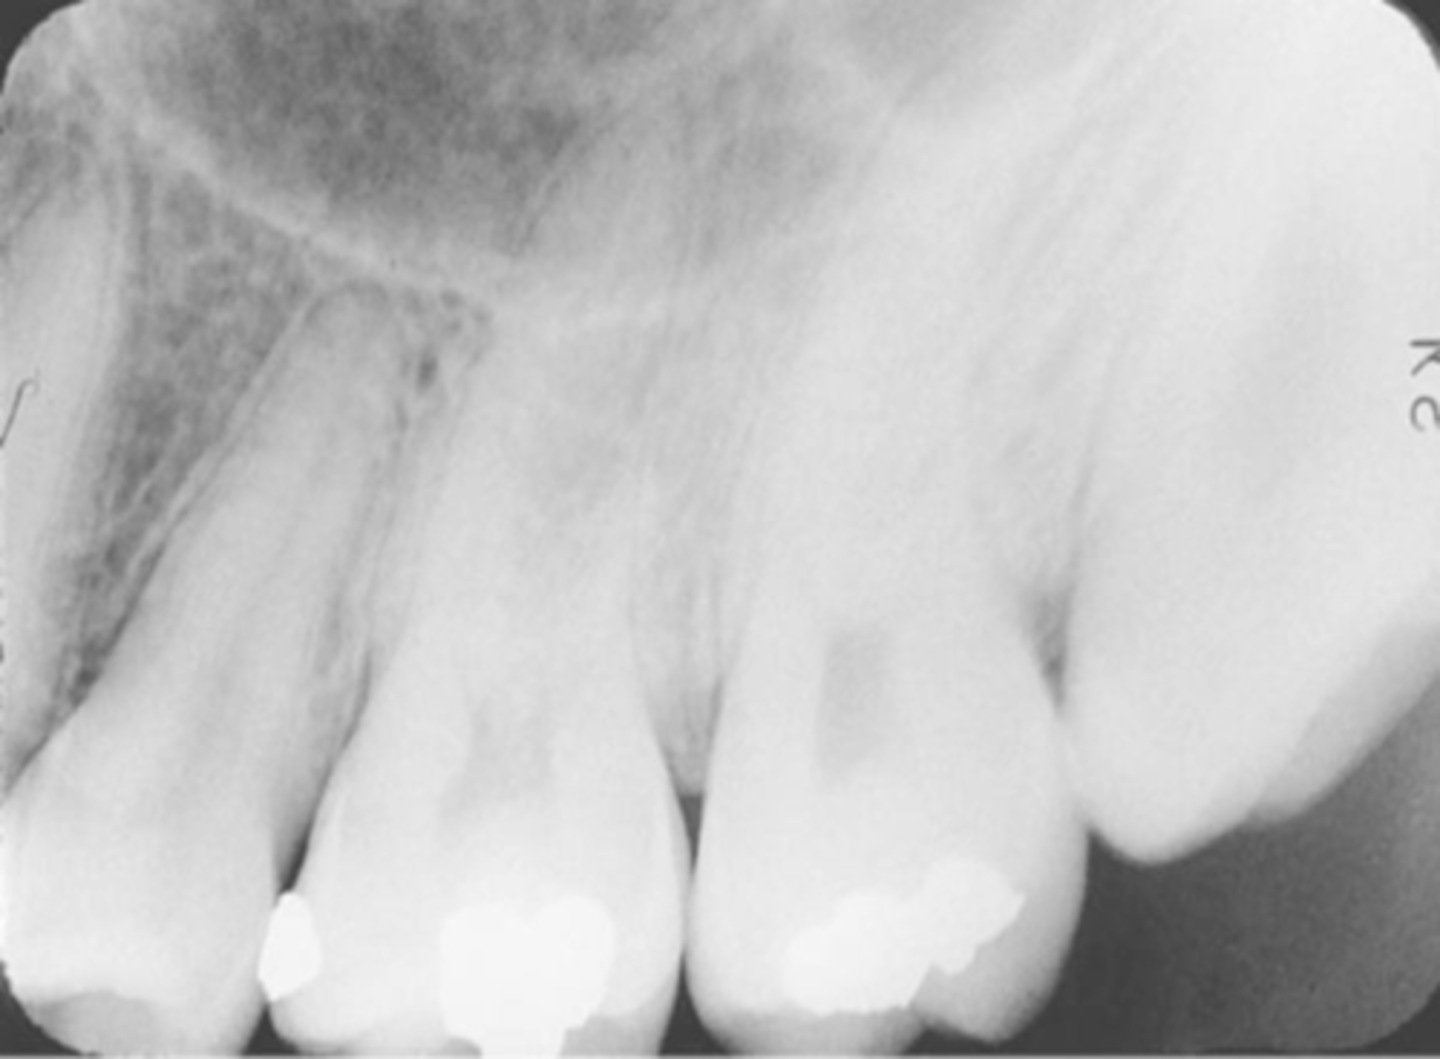

overlapped contacts

contacts are overlapped

central ray not directly through the interproximal spaces